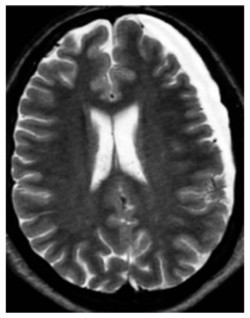

Fracture de Jefferson au niveau de l’arc antérieur C1 (première vertèbre) et élargissement du canal rachidien secondaire à la fracture de l’arc antérieur de C1.

Les radiographies peuvent détecter plusieurs fractures cervicales, telle que la fracture de Jefferson au niveau de la deuxième vertèbre. Ce type de fracture crée une ouverture de l’anneau de la première vertèbre et, en conséquence, un élargissement du canal rachidien (conduit à l’intérieur de la moelle épinière). Il est possible de voir une entorse grave des deux premières vertèbres. Ce trauma est souvent lié à une hyperflexion du cou, ce qui donne lieu à une lésion du ligament transverse empêchant un frein postérieur. Une partie de la première vertèbre cervicale se déplace alors vers l’arrière et comprime le canal spinal. Il est donc possible de voir, sur une radio de profil, le déplacement de l’arc antérieur de C1 et la face antérieure de l’odontoïde.